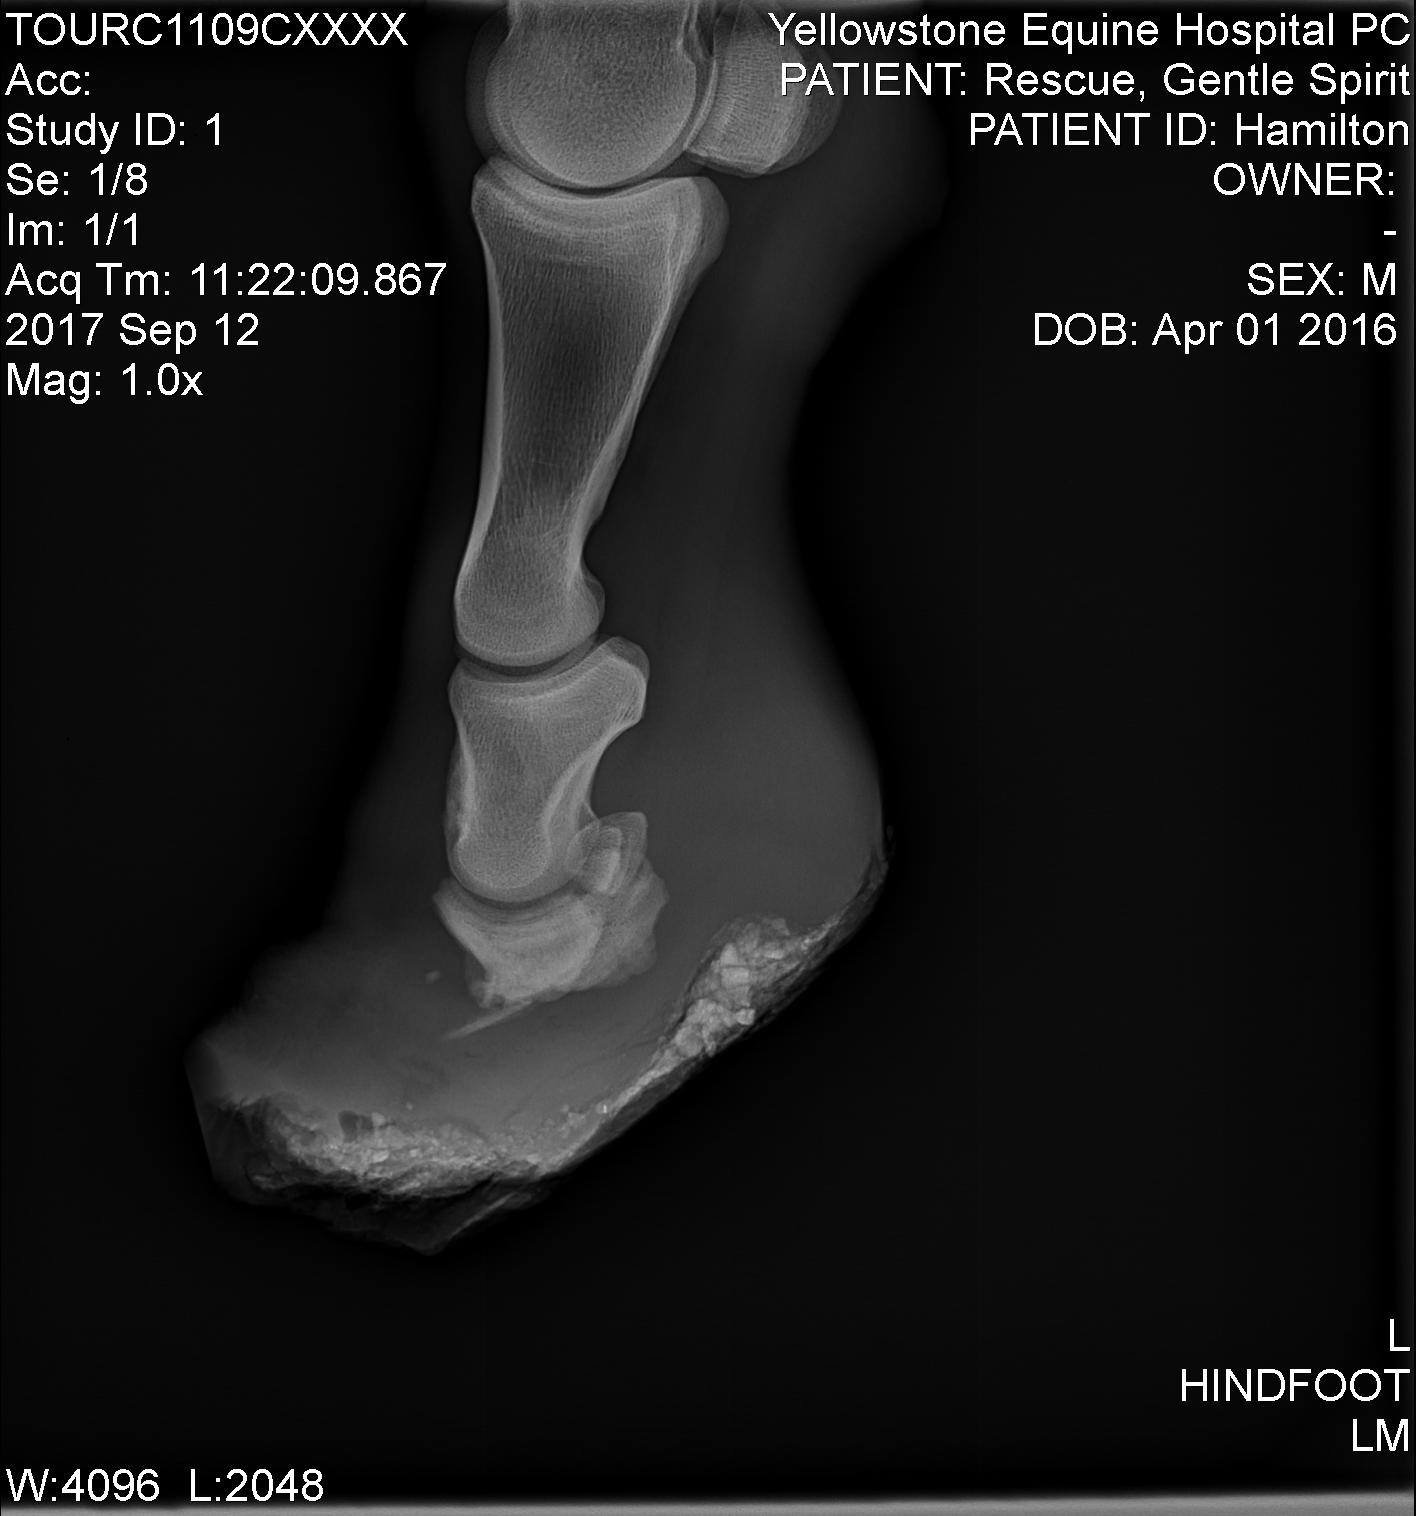

We’ve had a few horses like that over the years. One of them, Hamilton, was born with a severe congenital defect involving both hind feet. His birth defect was the result of overcrowding, inbreeding, and lack of care in a large-scale neglect case. His case was so unusual that it became part of international veterinary conversations. We worked closely with one of the top lameness and surgical experts in the country, and Hamilton’s x-rays and case details were shared with specialists, radiologists, and educators across the world. He taught not only us, but many others—and we kept his vet updated on his life, his challenges, and ultimately, our decision to let him go when his body could no longer compensate. We chose time as long as he remained comfortable. When that changed, we made the call. But what we learned during those nine years has stayed with me—and, I hope, informed others as well.